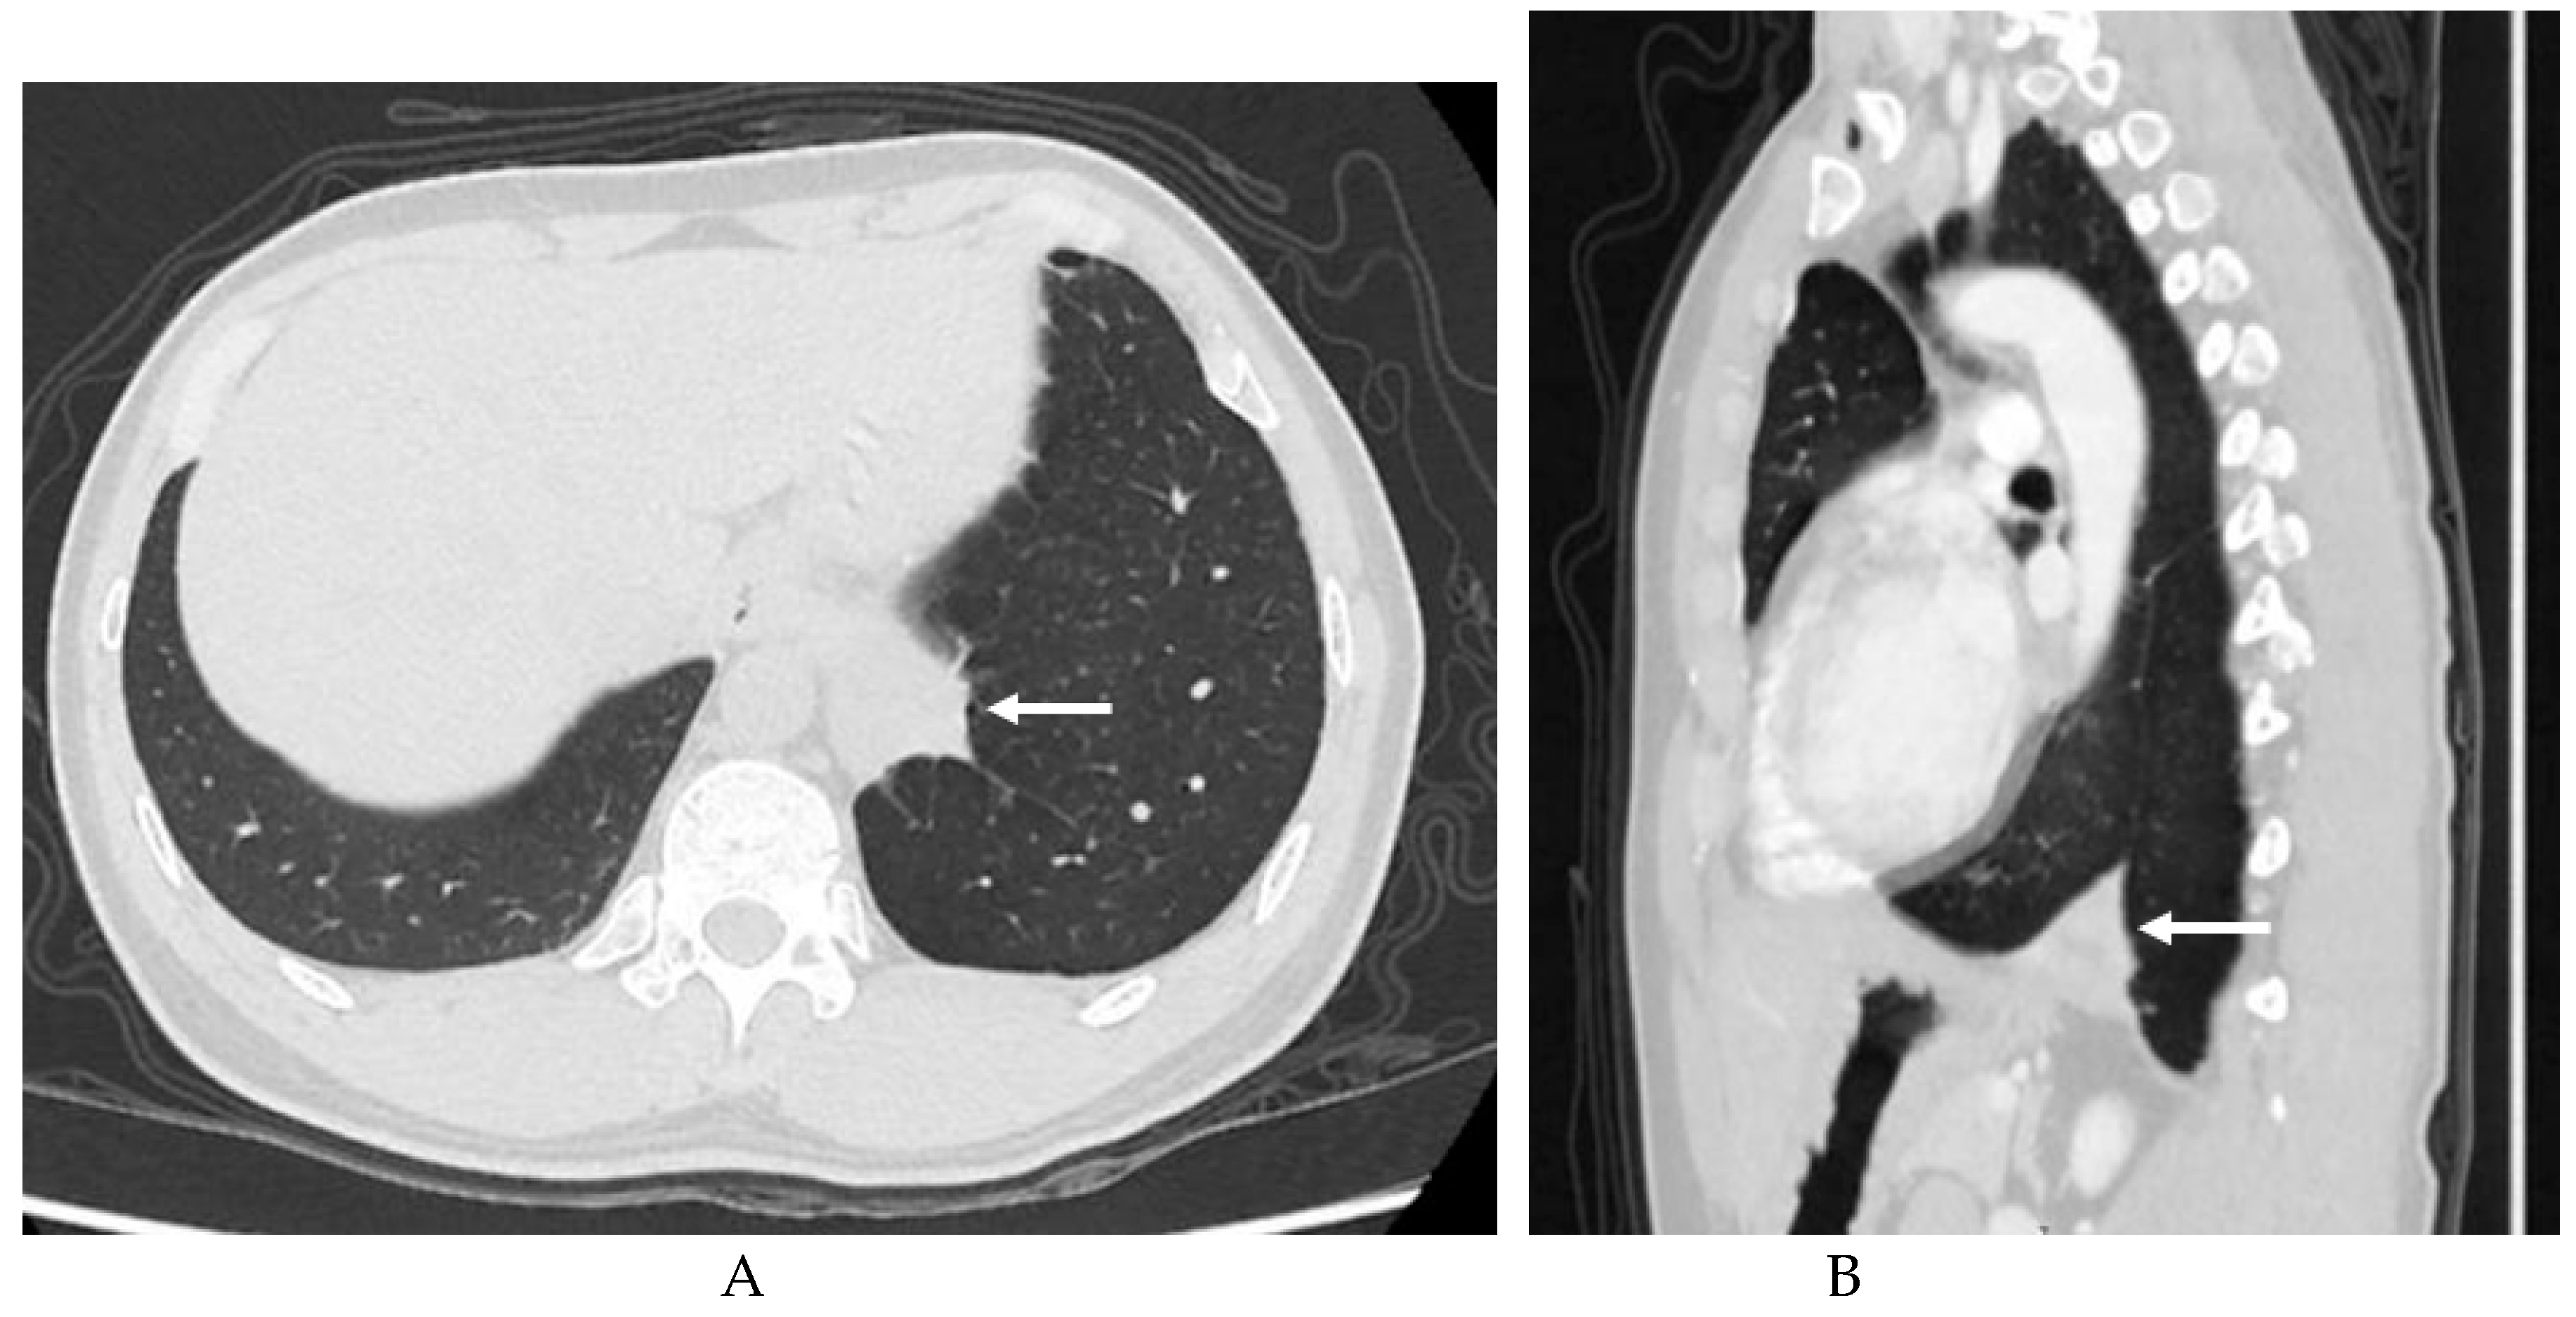

3.2. Imaging appearances of CTPA